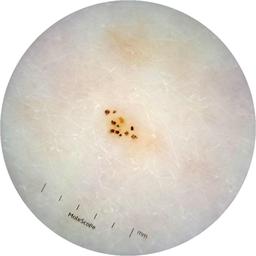

ISIC_6363669

MEL-SELF Trial, https://www.sydney.edu.au/medicine-health/our-research/research-centres/melself-project.html

Clinical

Field Value

acquisition_day 264

age_approx 65

anatom_site_1 Trunk

anatom_site_2 Anterior trunk

anatom_site_general anterior torso

concomitant_biopsy False

diagnosis_1 Benign

diagnosis_confirm_type single image expert consensus

family_hx_mm True

image_manipulation instrument only

image_type dermoscopic

lesion_id IL_2591344

patient_id IP_1322385

personal_hx_mm True

sex female